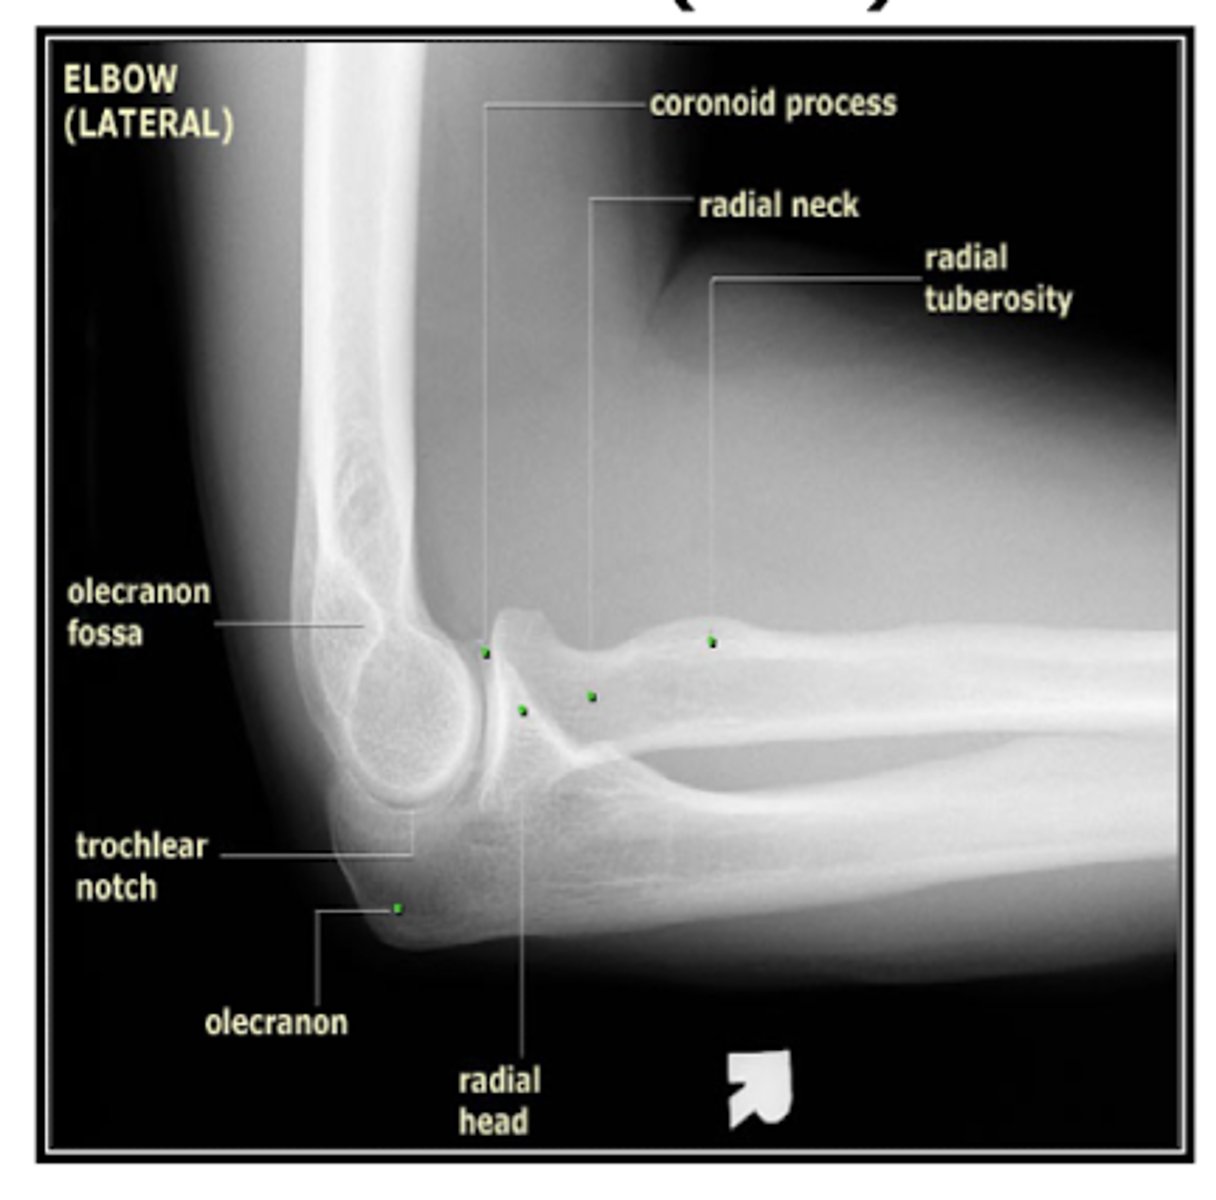

REVIEW: XR of elbow (lateral view)

What does a fat pad sign/sail sign on elbow XR suggest? What type most common in adults and children?

presence an articular hemorrhage due to an occult or intra-articular fracture

Adults → radial head Fx

Children → supracondylar Fx of humerus